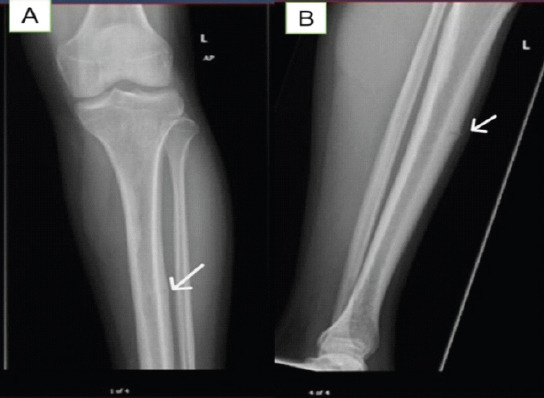

Case report: Here, we discuss a rare clinical case of a sportsman who presented in our hospital. A 26-year-old professional football player presented to us in July 2024 with bilateral leg pain which worsened on playing football. The plain radiograph showed that the middle part of the left side tibial shaft anteriorly had higher density, while the right side was unremarkable; which was further investigated with computed tomography scan on left side on presentation and magnetic resonance imaging on right side on 3 months follow up.